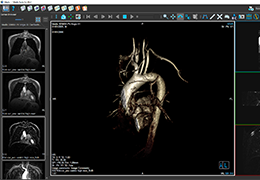

View X-Ray CT & MRI Scans Fast and Easily

Designed for surgeons, Pro Surgical 3D makes it easy to view patient scans quickly. Pro Surgical 3D facilitates the optimal 3D treatment and assessment workflows based on X-ray CT and MRI scans – and best of all, it’s FREE!

High-quality and fast 3D reconstruction and 3D rendering

Performs 3D reconstruction and volume rendering.

Instant and interactive surface extraction and export to STL and PLY formats.